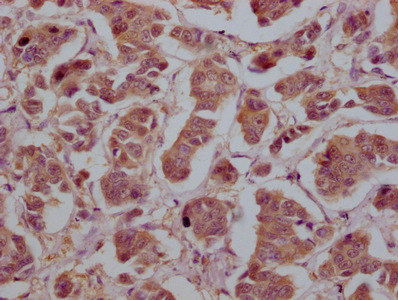

IHC image of CSB-MA026293A0m diluted at 1:200 and staining in paraffin-embedded human liver cancer tissue performed on a Leica BondTM system. After dewaxing and hydration, antigen retrieval was mediated by high pressure in a citrate buffer (pH 6.0). Section was blocked with 10% normal goat serum 30min at 37°C. Then primary antibody (1% BSA) was incubated at 4°C overnight. The primary is detected by a Goat anti-rabbit IgG labeled by HRP and visualized using 0.05% DAB.